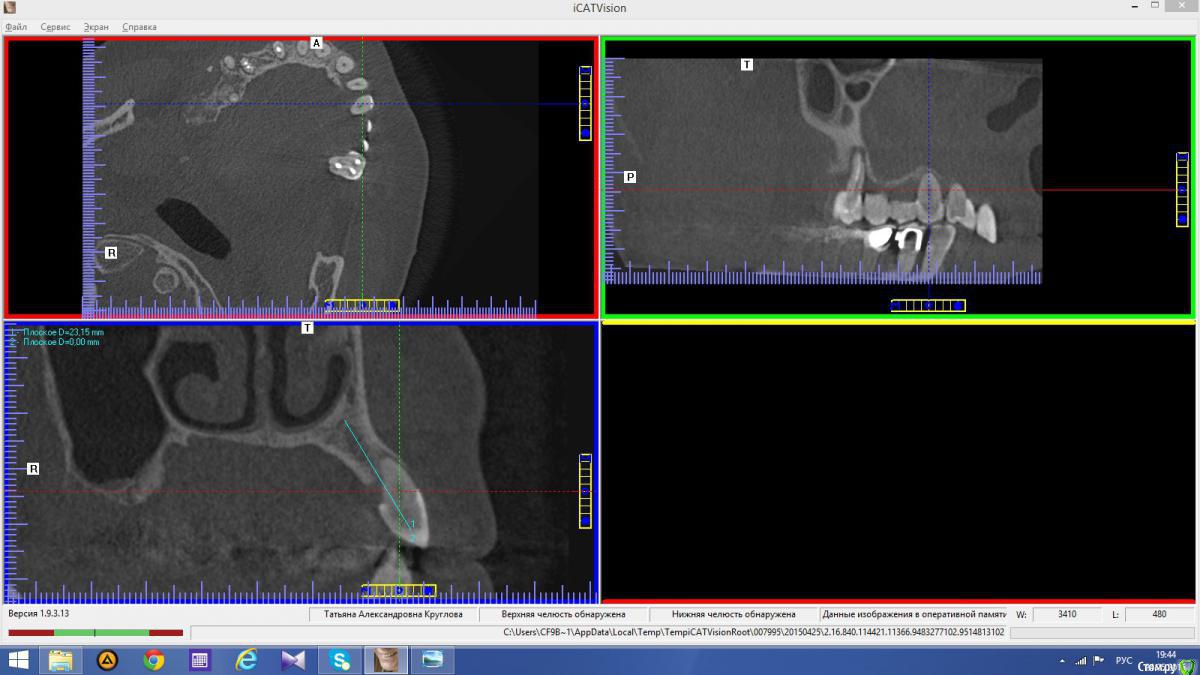

anvladd Опубликовано 24 ноября, 2015 Поделиться Опубликовано 24 ноября, 2015 Снимки не могли бы показать? Ссылка на комментарий

Abuk Опубликовано 24 ноября, 2015 Автор Поделиться Опубликовано 24 ноября, 2015 Снимки не могли бы показать? .все что есть готовое. Ссылка на комментарий

Abuk Опубликовано 24 ноября, 2015 Автор Поделиться Опубликовано 24 ноября, 2015 (изменено) Радикально Вы. Что оставили ей после имплантации-это инд аббатменты? На них мокап одели и нагрузили сразу? У всех был торк хороший? Или это временные абб? Что за систему использовали? В планах консоль назад, правильно я понимаю?Спасибо.увидев такую работу,сам так же подумал бы). Но там подвижность 2-3 ст. ближе к 3. Мосты болтались ,2 ки в хлам. 1 ки только стабильны. Снимал мосты,проводил кюретаж. Решил дернуть.Абатманы временные, тех. сделал на них коронки. Система анкилоз. Работа,на посл. фото, постоянная . Имплы в области 4 и по одному моляру ,консоли. Мок ап был до имплантации . По нему шаблон. Стабильность 15 -20 на 23 , остальное больше 30. Изменено 24 ноября, 2015 пользователем Abuk 1 Ссылка на комментарий